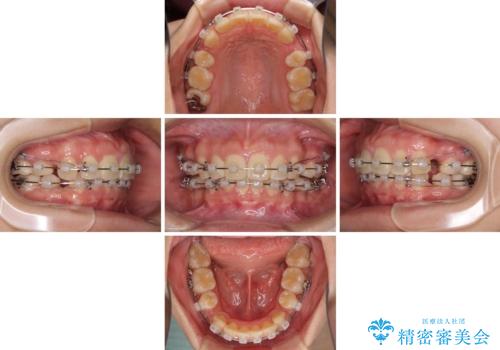

- クリアブラケット

- 2年5ヶ月

- 10-30回